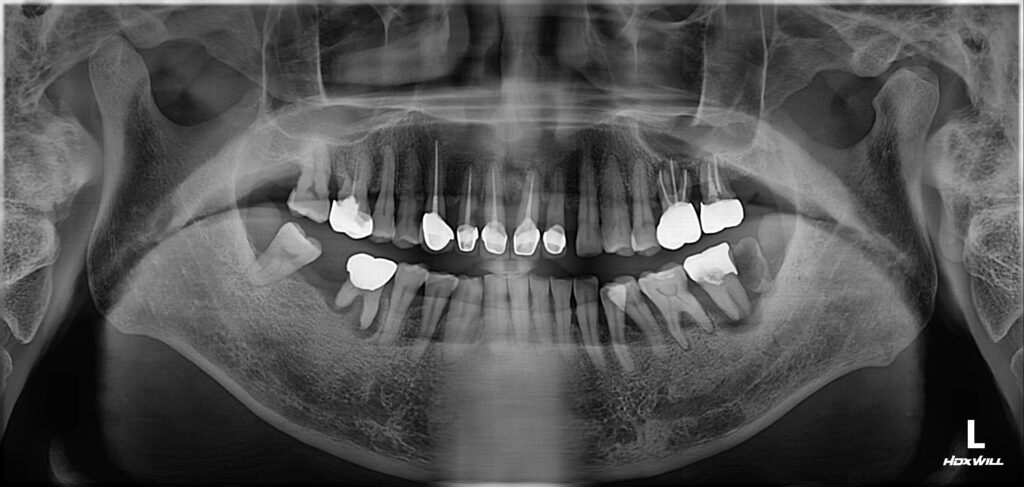

60대 남성분께서 치아 전체가 아프다며 치과에 내원하셨습니다.

상태는 아래와 같았어요.

어금니뿐 아니라 앞니 쪽에도 심한 치주 질환으로(잇몸질환) 치아가 많이 흔들리고 부어 있었습니다.

어금니는 아파서 씹지를 못하고 앞니는 흔들리기도 하지만 심미적으로도 안 좋아서 일상생활이 힘드신 상태였습니다.